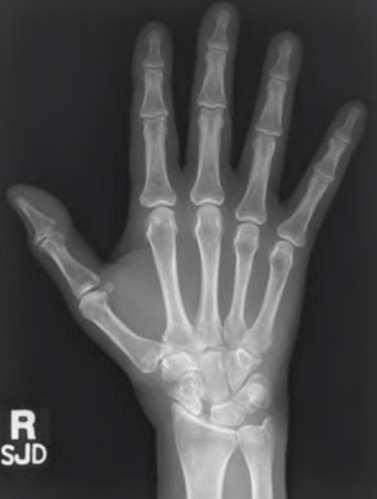

A 20-year-old park ranger trips and falls onto his right wrist with the wrist in extension and pronation. The local urgent care orders both radiographs and a CT, which you review and determine to be normal. The patient complains of ulnar-sided wrist pain. On exam, his tenderness is localized to the fovea. Ulnar deviation also causes him pain. There is no snapping sensation with wrist supination, flexion, and ulnar deviation. He otherwise has 5/5 strength to his first dorsal interosseous muscle with 4mm static two-point discrimination on the ulnar side of the 4th digit. Which of the following injuries is most likely responsible for his symptoms and exam?